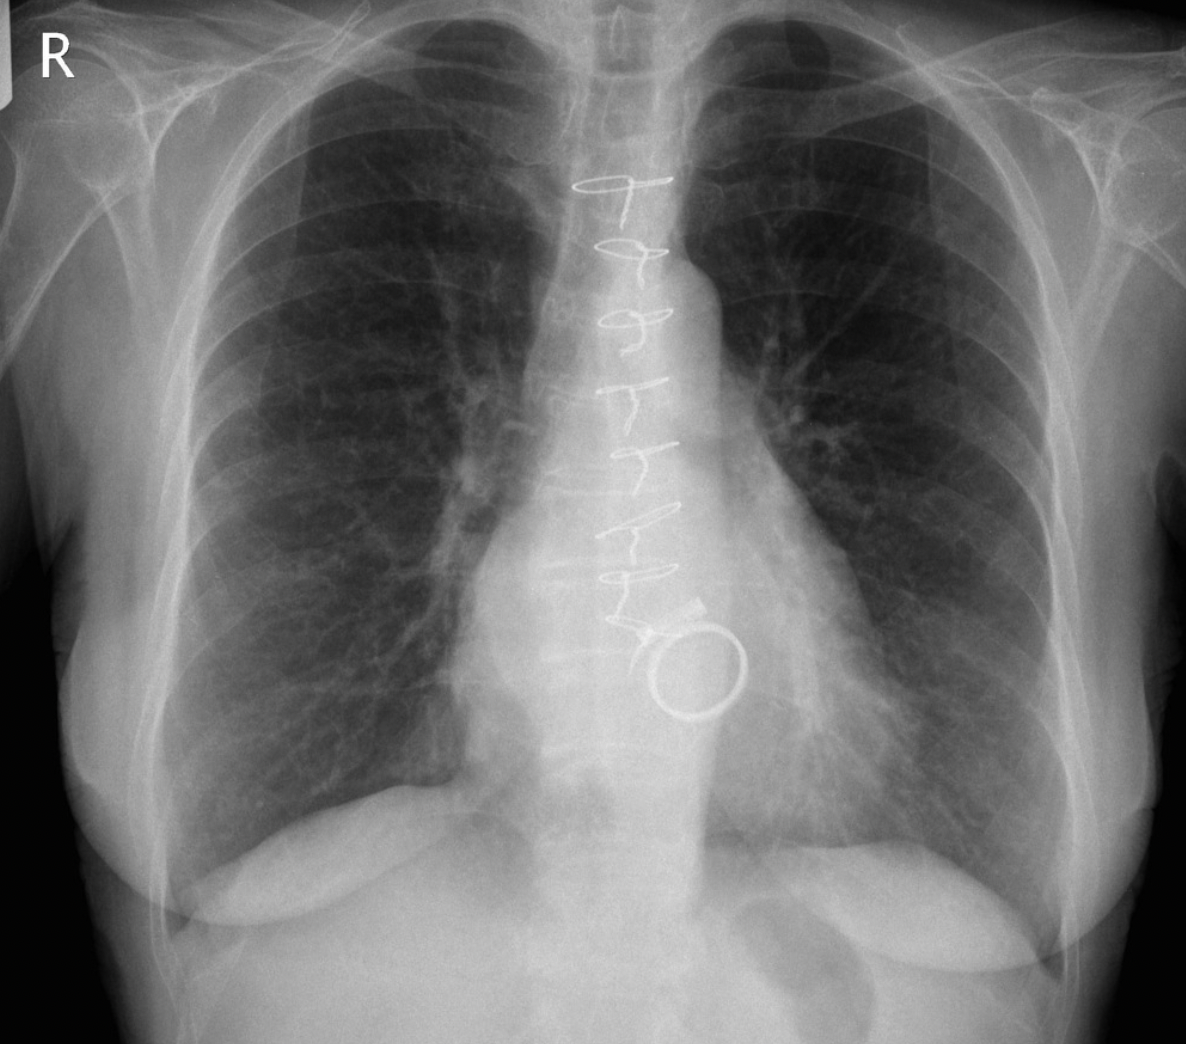

2

Q

A

Scimitar syndrome (Anomalous right lower pulmonary vein draining into IVC)